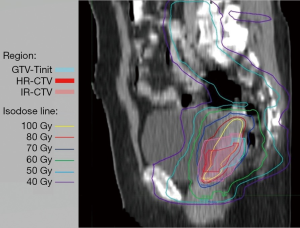

The cumulative dose distributions, comprising EBRT and four sessions of ICBT, were successfully illustrated using DIR (Figure 2). The HR-CTV was covered with 70–80 Gyα/β=10. The parametria were covered with 50–60 Gyα/β=10.

DIR accuracy is of utmost importance in evaluating the DIR-based cumulative dose distributions and DVHs of the tumor and OARs. All selected cases in the present study had anteflexed or upright uterus. The uterus became horizontal after the insertion of the uterine tube in the ICBT. Considering the comfort of patients without general anesthesia in every ICBT session, the patients were only required to collect urine during ICBT to stabilize bladder size and position. With these methods, the cumulative images by rigid fusion were based on the bony structure (Figure 2).